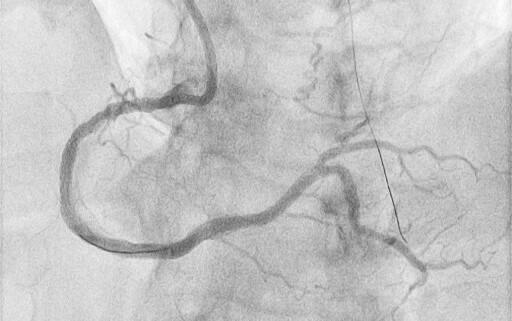

Thrombotic Complication After a Double-Barrel Configuration Percutaneous Coronary Intervention in a Chronic Total Occlusion